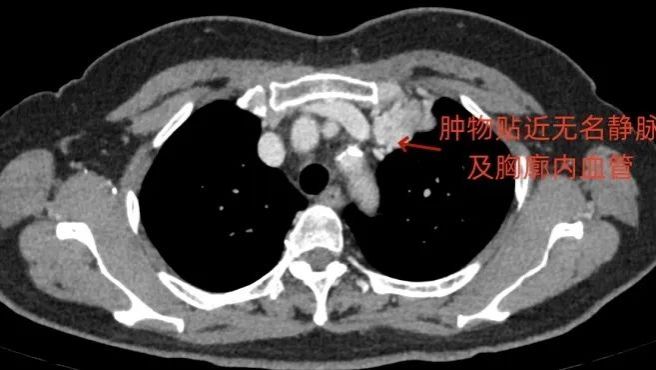

无独有偶,近期胸外科还联合心脏外科完成了另外一例复杂的胸腔肿瘤手术。付女士是一位70岁的老年女性,2024年3月因为反复咳嗽就诊,胸部CT检查发现,心脏的侧前方有一个巨大肿瘤。肿瘤与一些无名静脉、胸廓内动静脉等关键血管以及肺门的关系非常密切。

患者术前胸部CT增强

经过医生评估,手术切除是效果最佳的治疗方法,但术中需要保护上述脆弱的血管,存在很大的难度与风险。胸外科与心脏外科术前讨论,决定采用正中开胸入路,必要时转为"T"字切口,确保肿瘤安全切除和血管保护。手术中采用左侧封堵器麻醉,关键步骤时左肺萎陷以利切除。